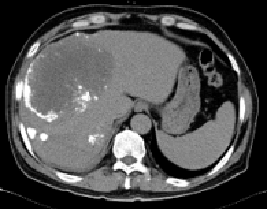

影像学检查:

腹部CT平扫+增强(2014-04-24):肝右叶巨块型肝Ca伴肝内多发转移可能(肿瘤直径15.5cm)

原发性肝癌 (BCLC B期)